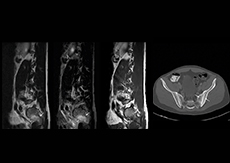

More information without extending time slot

“In our lumbar spine MRI, the value of mDIXON TSE is so obvious. Normally we perform T1 and T2 scans in sagittal and transverse orientation.It used to take too much time to add a sagittal T2 with good fat suppression.But now, using mDIXON TSE, we get the sagittal T2 fat suppressed images ‘for free’, that is: without adding time.” “Diagnostically that is a great benefit. I sometimes see abnormalities in the fat suppressed sagittal T2 that would be quite challenging to notice in the T2 without fat suppression. There have been several diagnoses that I could make easier because of our exam setup with mDIXON TSE, such as sacrum insufficiency fractures and sacroileitis; these were more challenging with our previous exam setup.”